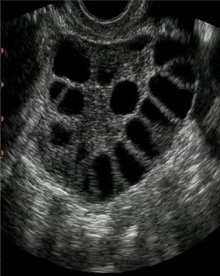

What is PCOS?

Polycystic ovarian syndrome is characterized by many pearl sized follicles growing and dying with out ovulation.

PCOS treatment

Burn the stroma to decrease estrogen levels so ovulation can occur.